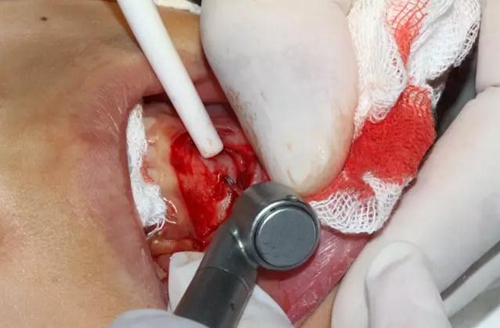

切開、翻瓣

去除骨皮質(zhì),暴露牙冠大部分

設(shè)計(jì)冠切的位置

橫斷牙冠,注意深度的把控